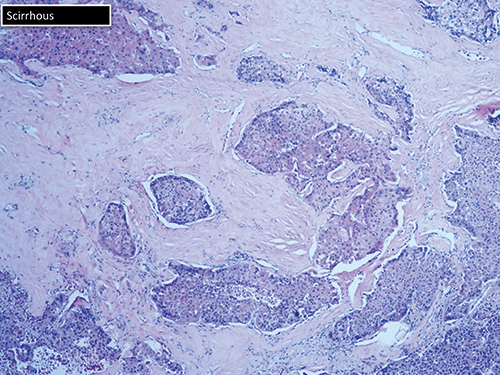

The scirrhous variant can be mistaken for cholangiocarcinoma (Fig. 7). “Just by looking at it, they call it high-grade cholangio. And you may need to do your hepatocellular stains.” The markers of liver origin are HepPar1, arginase 1, polyclonal CEA, and glypican 3.